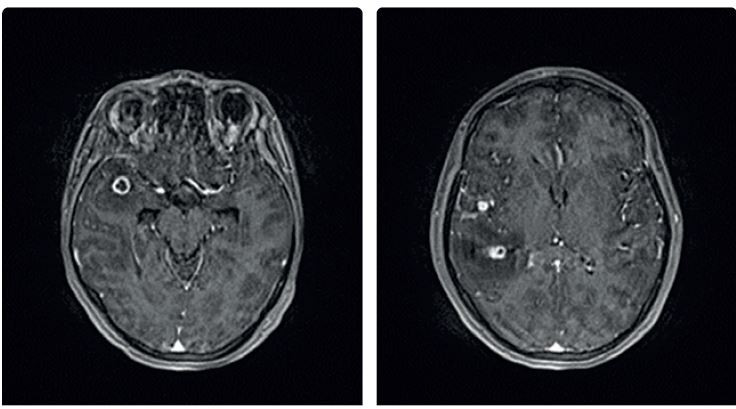

Diagnóza tuberkulózy se opírá o anamnézu, klinické symptomy, patologický radiologický nález a zásadní význam má bakteriologický průkaz patogenu ve vyšetřovaném materiálu. Radiologický nález u TB bývá charakteristický, ale nikoli specifický (obr. 2). Radiologicky může tuberkulóza imitovat jakékoliv plicní onemocnění. Nicméně zadopřední skiagram hrudníku doplněný o boční projekci je základním vyšetřením u plicní i mimoplicní TB. Pokud u pacienta s patologickým radiologickým nálezem není ve sputu M. tuberculosis jednoznačně prokázáno, doplníme k upřesnění nálezu vyšetření výpočetní tomografií (CT) s vysokým rozlišením (HRCT hrudníku). V případě podezření na mimoplicní TB indikujeme zobrazení ostatních tkání a orgánů – magnetickou rezonanci (MR) centrálního nervového systému (CNS), skiagramy či CT, ev. MR kostí, vylučovací urografii, CT břicha apod. (obr. 3).